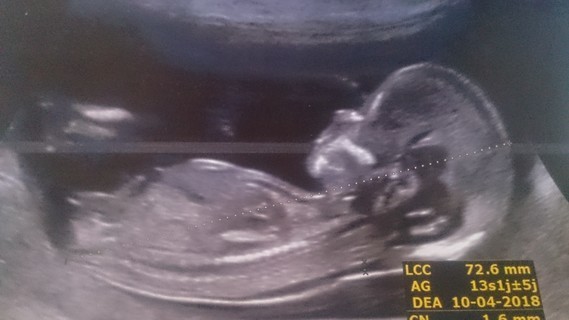

Savoir le sex du bebe echographie

Savoir le sex du bebe echographie-1 Test des mainsTout le monde ira de ses prédictions Pourtant, ce n'est que l' échographie qui vous révélera ce grand secret En attendant ce jour, voici 15 trucs pour prédire le sexe de bébé Attention!

Mais prudence, tout dépend du moment où l'échographie est réalisée et du temps que le praticien prend pour examiner le sexe Sachant que la première échographie a un objectif bien défini (nombre de fœtus et localisation, vitalité du fœtus, clarté nucale , anatomie), l'identification du sexe n'est clairement pas la prioritéCette façon de faire estelle fiable ?Fille ou garçon comment savoir ?

La détermination est parfois possible dès le 3ème mois Comment savoir si on est enceinte d'une fille ou d'un garçon?Savoir le sexe de bébé avec le NIPT pas toujours possible selon les pays Mais ça n'est pas tout, le DPNI permet aussi de connaître le sexe de l'enfant Bien sûr, ça n'est pas l'objectif premier de ce dépistage, et si vous vivez en France, vous ne pourrez pas savoir le sexe uniquement « pour le plaisir », pour des raison